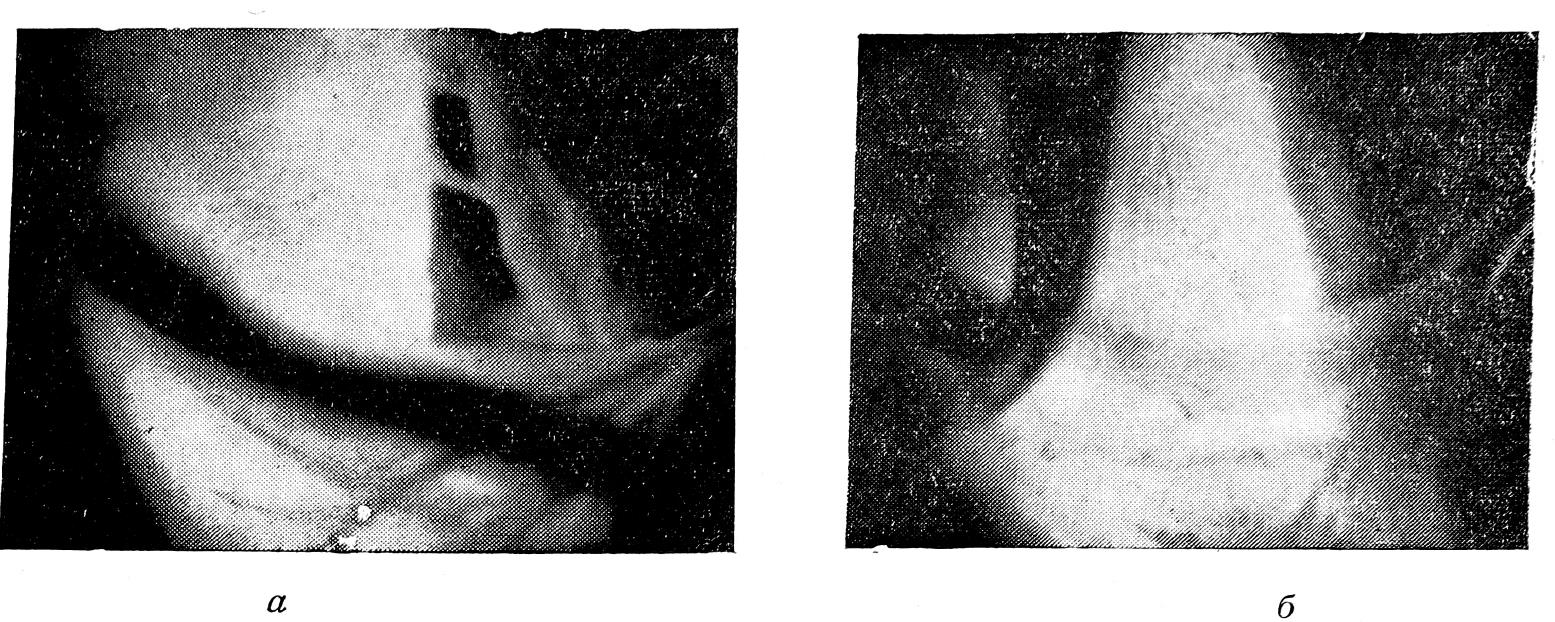

Трансиллюминация обеспечивает «оптическую препаровку» тканей. Фиксированные к стенке трахеи лимфатические узлы дают интенсивные затенения с четкими контурами (рис. 6).

Рис. 6. Теневые изображения в претрахеальном канале при просвечивании трахеи, заснятые на трупе (а) и в опыте на собаке (б). Просветленные с поперечной исчерченностью поля соответствуют стенке трахеи. Интенсивные овальной формы затенения связаны с лимфатическими узлами.

На основании характерных теневых изображений облегчается идентификация кровеносных сосудов разного диаметра. Контрастирование сосудов при трансиллюминации обусловлено циркулирующей в них кровью. Наши исследования показали, что стенки сосудов (артерий и вен) из-за физических свойств проходимы для лучей видимого света. В связи с этим освобождение тем или Иным путем сосуда от крови резко меняет трансиллюминационную картину. На рис. 7, а приведена теневая картина, заснятая в проксимальном отделе претрахеального канала в опыте на собаке. Плечеголовная артерия и фасция оставлены на трахее. Последней соответствует освещенное удлиненное поле. Артериальный ствол отчетливо определяется в виде интенсивного лентовидного затенения с четкими контурами. Освобождение просвета сосуда от крови ведет к изменению теневой картины (рис. 7, б) —стенка сосуда из-за значительной прозрачности дифференцируется нечетко. Заполнение сосуда кровью восстанавливает исходное трансиллюминационное изображение.

Рис. 7. Трансиллюминационные картины в проксимальном отделе претрахеального канала. Опыт на собаке. Изображение плечеголовной артерии в зависимости от наличия в ее просвете крови. Интенсивное лентовидное затенение — плечеголовная артерия, заполненная кровью (а). Сосуд, освобожденный от крови, в тех же условиях дифференцируется нечетко (б).